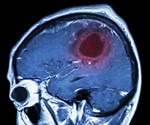

Cerebral palsy refers to a number of neurological conditions that affect muscle control and movement. Children with cerebral palsy have difficulties in controlling their muscle movement as they grow and develop.

Cerebral palsy is a term that encompasses several neurological conditions that affect a child's movement and coordination. It mainly occurs due to damage to the brain that may occur before, during or soon after birth.